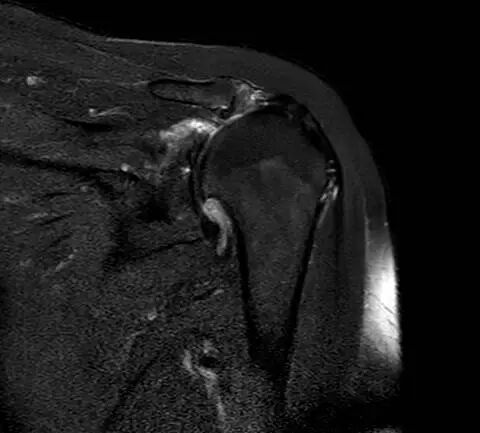

▲患者肩关节平片及MR提示巨大肩袖撕裂、肱骨头半脱位、骨关节炎

年逾古稀的施阿姨发现自己的左胳膊近几年来越来越“不来事”了,不仅疼痛逐渐加重,连抬手梳头、正常穿衣都难以完成,而膏药、按摩等治疗手段也失去以往的效果。来到同济大学附属同济医院就诊后,经过运动医学科程飚主任的详细查体,他发现施阿姨的病情并非常见的“肩周炎”,而是巨大、无法自行愈合的肩袖撕裂,并且肩部骨头之间失去缓冲,已磨损成为严重的肩关节炎。